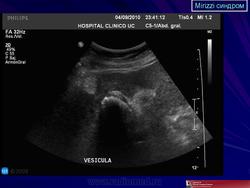

Все больные повергались общеклиническому обследованию, проводилось эндоскопическое исследование верхних отделов желудочно-кишечного тракта. УЗИ желчного пузыря, внутри- и внепеченочных желчных протоков, печени и её ворот, поджелудочной железы, а также желудка и двенадцатиперстной кишки производили с использованием аппарата Philips HDI 4000, в режиме реального времени. Использовали линейные и секторальные датчики с частотой 3,5 Мгц, а также допплеровский и энергетический датчики.

Результаты исследования и их обсуждение. Оценивая результаты УЗИ, которое было выполнено до операции, следует отметить, что использование новейшего ультразвукового сканера Philips HDI 4000 позволило у 89 (67,4%) пациентов установить диагноз синдром Мириззи. При оценке эхограмм нами придавалось значение размерам и расположению конкремента в желчном пузыре, интимному прилеганию гартмановского кармана с расположенным в нем конкрементом к правому либо общему печеночным протокам, признакам сдавления конкрементом общего желчного протока, наличию расширения внутри- и внепеченочных желчных протоков (рис.1,2). При оценке результатов ЭРХПГ патогномоничным для синдром Мириззи считали характерное сдавление извне общего желчного протока, либо наличие холецистохоледохеального свища, что было установлено у 77 (58,3%) больных.